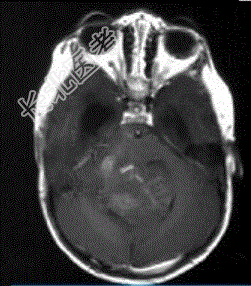

- 单项选择题成年男性患者,头痛、头晕、恶心, 病程2年余,结合影像图像选择最可能的诊断

A、星形细胞瘤

B、畸胎瘤

C、脑膜瘤

D、室管膜瘤

E、胶质瘤